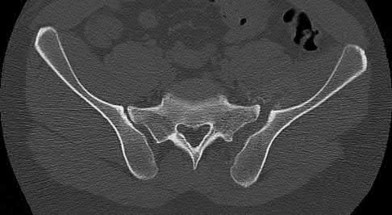

Which of the following images shows an injury pattern most consistent with a lateral compression type 3 pelvic ring injury?

Figure C is an axial CT scan of a lateral compression type 3 (LC3) pelvic ring injury.

Classically, LC3 injuries demonstrate an ipsilateral lateral compression and a contralateral APC (windswept pelvis) fracture pattern. The most common mechanism of injury in these cases is a rollover MVC or pedestrian vs. auto. LC1 injuries are characterized by an oblique or transverse ramus fracture and ipsilateral anterior sacral ala compression fracture, while LC2 injuries consist of a rami fracture and ipsilateral posterior ilium fracture dislocation (crescent fracture). While LC1 injuries can often initially be managed conservatively with protected weight-bearing and close observation, LC2 and LC3 pelvic ring injuries are almost universally operative.

Answer 1: This represents a lateral compression type 2 injury. Answer 2: This represents a lateral compression type 1 injury.

Answer 4: This represents an anterior posterior compression type 2 injury. Answer 5: This represents an anterior posterior compression type 3 injury.